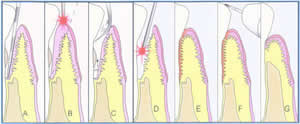

| A. A deep periodontal pocket, with loss of bone, and tartar on the root surface is determined to be present. |

| B. The laser selectively removes the infected gum tissue that lines the pocket wall, removing unhealthy tissue that lines the pocket for improved access to the pocket and the root surface. |

| C. Tartar and other debris is removed from the root surface, and rinsed out of the pocket. |

| D. The laser is used again to kill any bacteria or toxins that remain on the root surface or in the gum tissue, completely disinfecting the area. |

| E. The gum tissue is readapted back to the root surface and is seated to the root surface with a dense fibrin clot. We have a very small, sterile wound area that is now sealed shut. |

| F The bite is adjusted to eliminate any trauma to the tooth, and to balance out the chewing forces throughout the region. |

| G. Complete heating results in pocket depth reduction through reattachment of the gum tissue and connective tissue back to the root surface. |